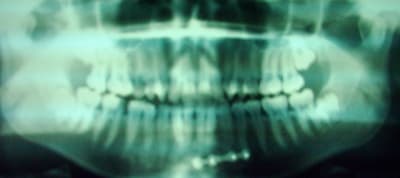

Voilà jeune patiente accident de voiture en mars, double fracture des condyles, non reduite, fracture de la symphise reduite avec plaques.

15 à extraire.

17 mobile.

Le problème est que la pano et les photos sont assez floues, j'aimerais voir une radio des condyles si c'est possible, mac peut-être qu'en mail les photos seront plus lisibles, envoie les et je te recontacte.

Pour les condyles j'ai les scanners mais je sais pas si je vais arriver à sortir les coupes.

Le scanner n'apporte pas grand chose quant à la position des condyles par rapport aux cavités glénoïdes, je préfèrerais voir les ATM sur la pano, ne peux tu pas en poster une meilleure que la première.

Je t'ai envoyé sur ton mail la pano, mais la radio en elle même n'est pas top.

J'ai regardé la pano et je ne vois pas suffisamment les condyles pour me prononcer, où se trouvent les fractures, y-a-t-il eu déplacement, sans doute non puisque les fractures n'ont pas été réduites.

Après consultation de mon prof, les questions qu'il m'a posées sont les mêmes que les miennes, quand à eu lieu l'accident, où ce situent les fractures, pourquoi n'y a t-il pas eu réduction?

L'accident a eu lieu en mars, les 2 condyles sont petés, il y a pas eu de reduction parce qu'elle tombé sur des idiots (à mon avis).